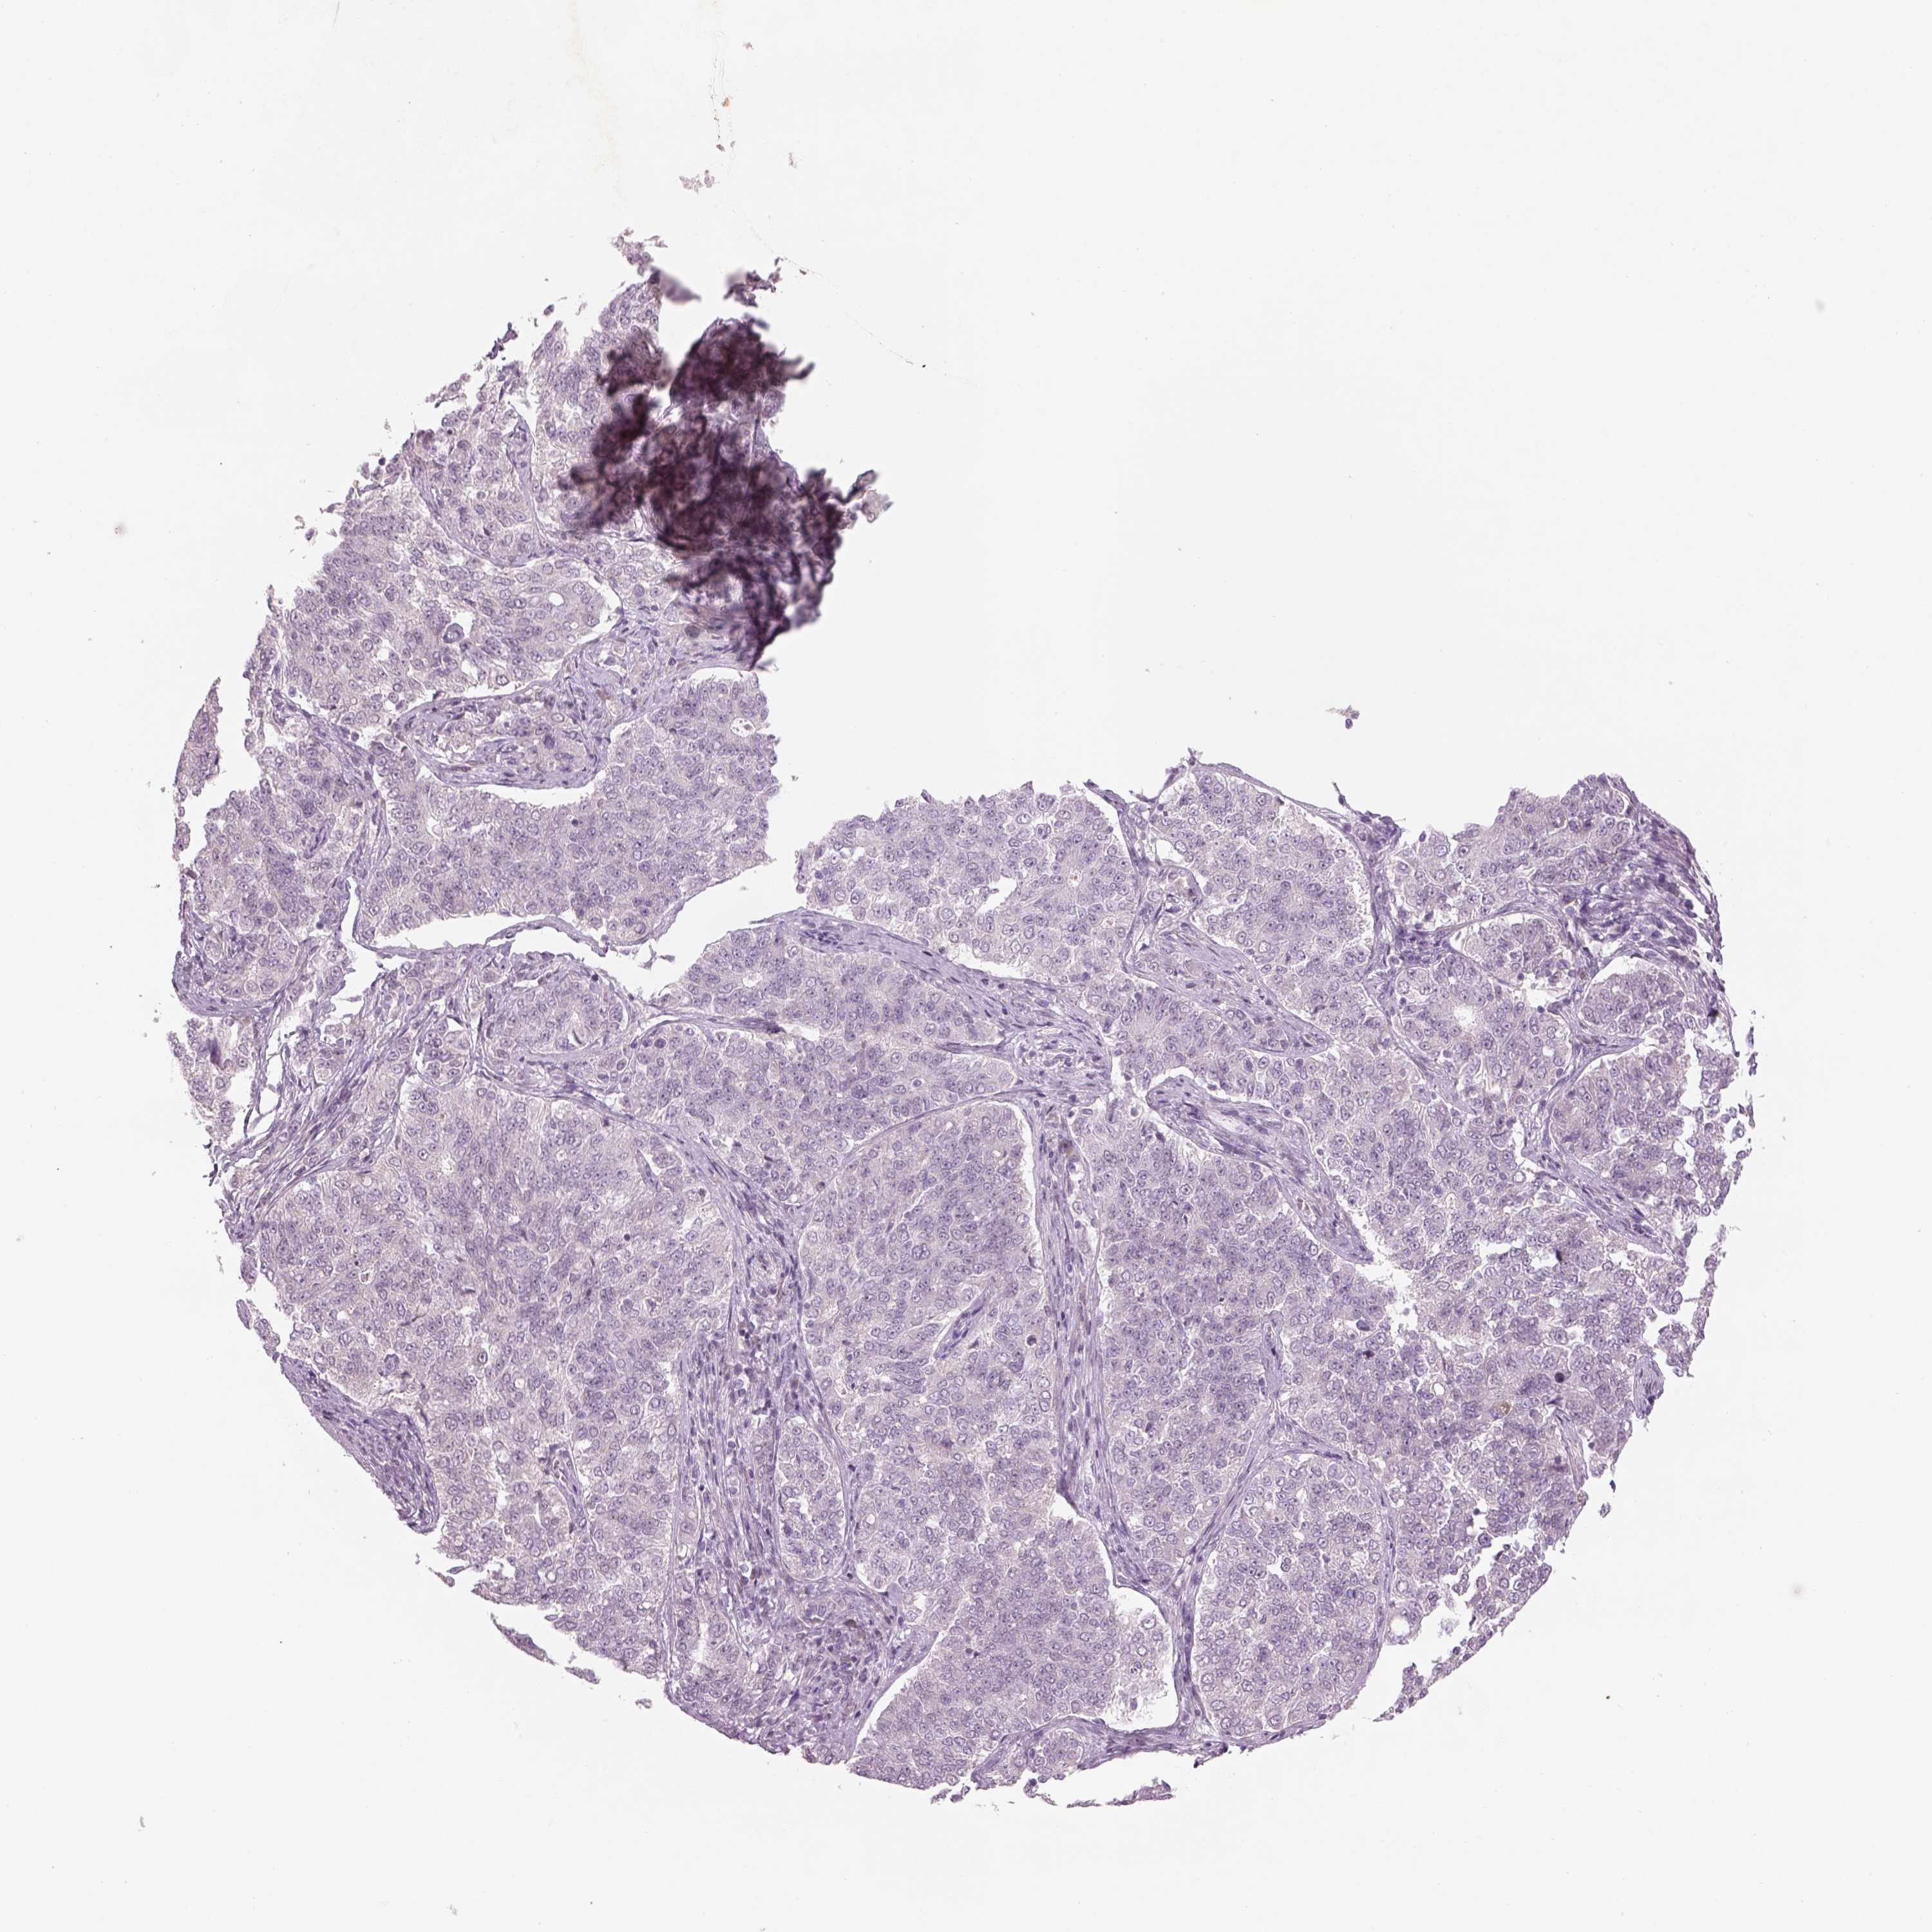

ENDOMETRIAL CANCER - Protein expressioni

A mouse-over function shows sample information and annotation data. Click on an image to view it in a full screen mode. Samples can be filtered based on level of antibody staining by selecting one or several of the following categories: high, medium, low and not detected. The assay and annotation is described here.

Note that samples used for immunohistochemistry by the Human Protein Atlas do not correspond to samples in the TCGA dataset.

Antibody stainingi

Antibody staining in the annotated cell types in the current human tissue is reported as not detected, low, medium, or high, based on conventional immunohistochemistry profiling in selected tissues. This score is based on the combination of the staining intensity and fraction of stained cells.

Each image is clickable and will lead to virtual microscopy that enables deeper exploration of all samples and also displays staining intensity scores, fraction scores and subcellular localization as well as patient and tissue information for each sample.

Antibody HPA013138

Antibody CAB016390

Staining

High

Medium

Low

Not detected

Intensity

Strong

Moderate

Weak

Negative

Quantity

>75%

75%-25%

<25%

None

Location

Nuclear

Cytoplasmic/membranous

Cytoplasmic/membranous,nuclear

Adenocarcinoma, NOS

Adenocarcinoma, metastatic, NOS